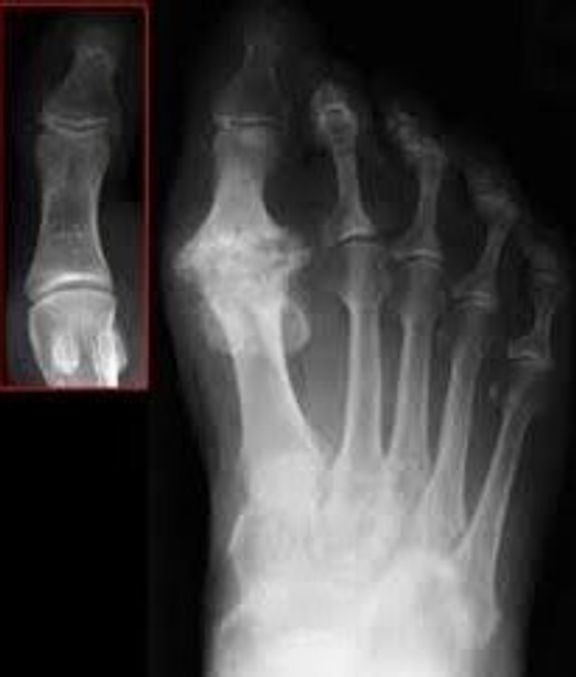

Hallux (great toe) limitus (diminished motion) is a condition in which the great toe cannot move through a normal range of motion during normal ambulation. Normal gait requires 65 to 75 degrees of dorsiflexion (ability to bend upward) at the base of the great toe. Any impairment in the fluid motion of this joint can be considered arthritis (“arthro” meaning joint and “itis” meaning inflammation). The name of this particular joint is called Hallux limitus. This progressive condition can eventually lead to losing all motion (Hallux rigidus) at the base of the great toe. The x‑ray image below compares a normal great toe joint with the full progression of the arthritis-associated Hallux rigidus.